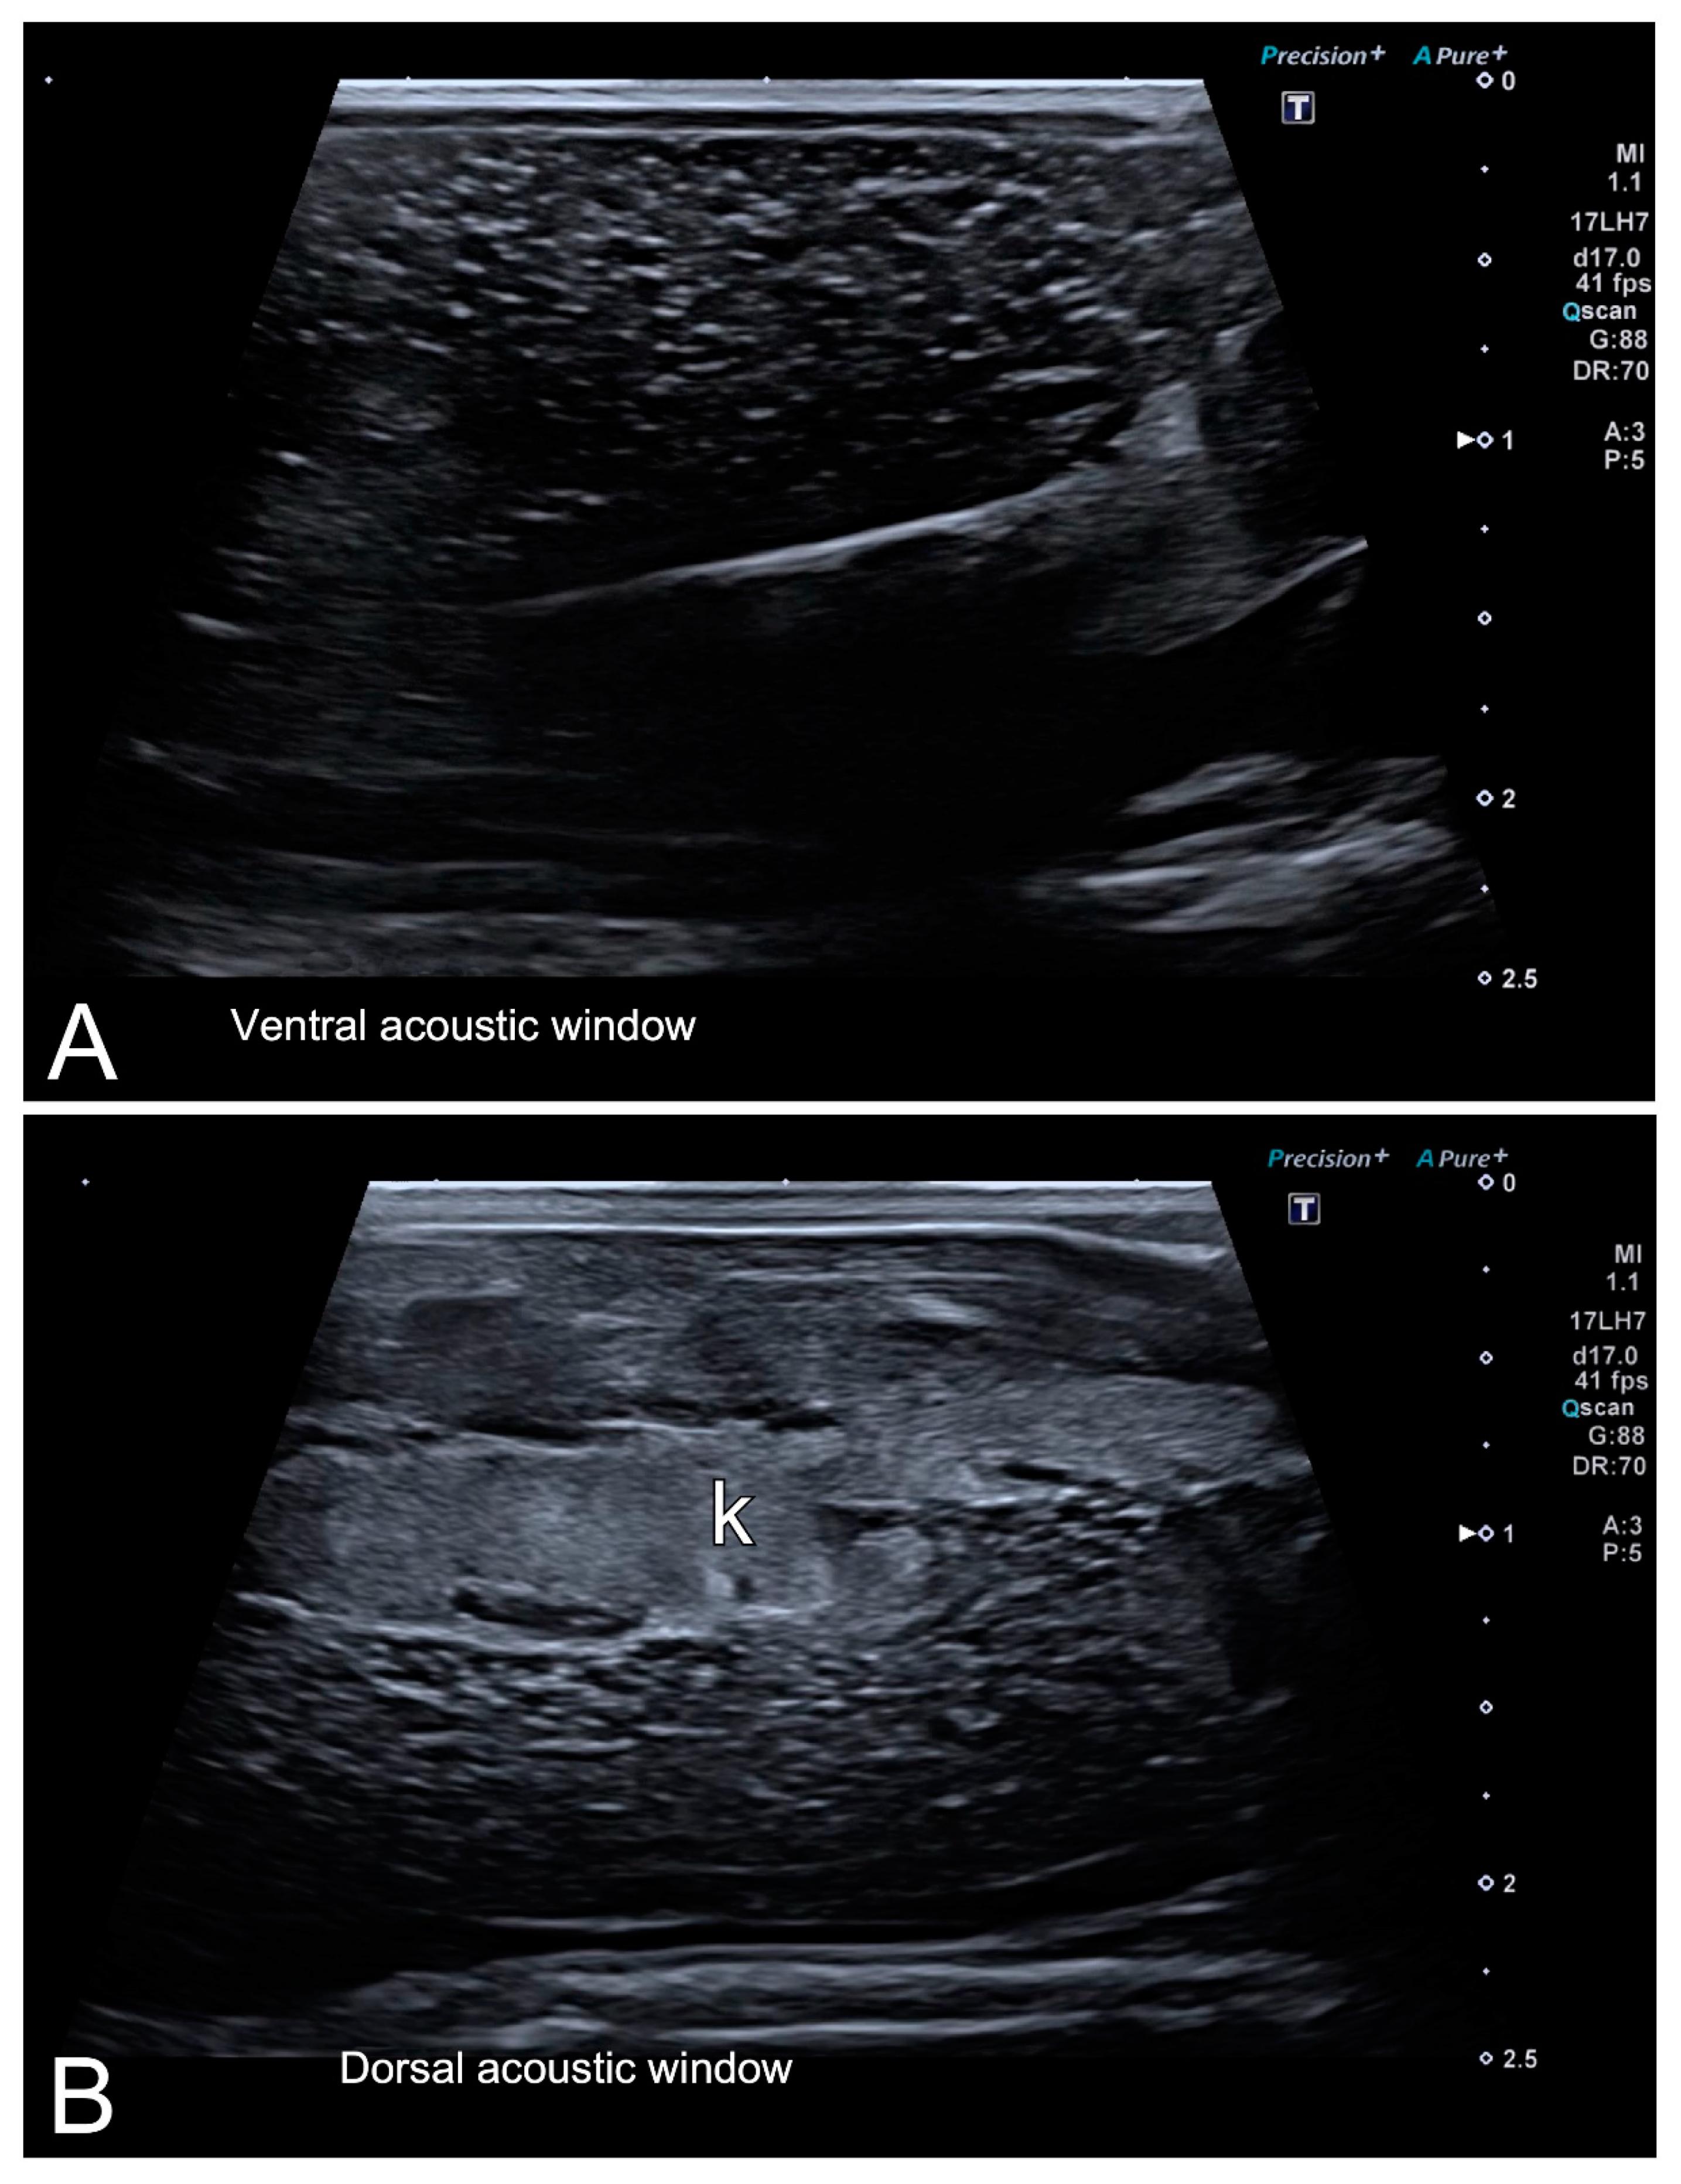

Figure 5. HR-US images of a female Xenopus laevis in the longitudinal plane using ventral (A) and dorsal (B) acoustic windows. Although the complex of follicles is clearly identified in both, the ventral acoustic window was considered more adequate for the examination of female gonads. Nevertheless, the kidney (k) was better identified using the dorsal acoustic window.

|